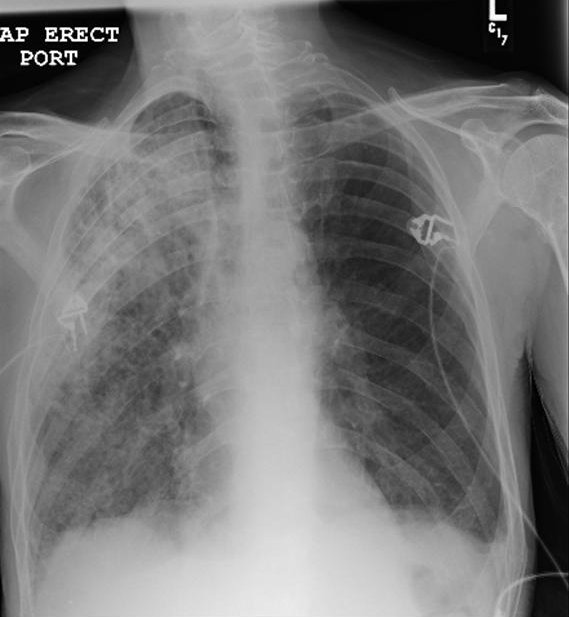

He was initially admitted to the general medical floor for treatment of community-acquired pneumonia (see Figure 1) and for the prevention of delirium tremens. He was initiated on ceftriaxone, azithromycin, thiamine and folic acid. Diazepam was initiated and titrated using the Clinical Institute Withdrawal Assessment for Alcohol Scale (CIWAS-Ar), a measure of withdrawal severity (1). By hospital day 5, his respiratory status continued to worsen, requiring transfer to the intensive care unit (ICU) for hypoxemic respiratory failure. His neurologic status had also significantly deteriorated with worsening confusion, memory loss, drowsiness, visual hallucinations (patient started seeing worms) and worsening upper extremity tremors without generalized tremulousness despite receiving increased doses of benzodiazepines.